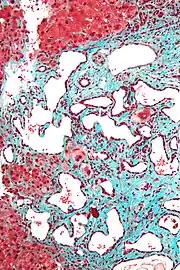

Micrograph of a bile duct hamartoma. Trichrome stain. Intermediate magnification

Low magnification micrograph of a bile duct hamartoma. Trichrome stain.